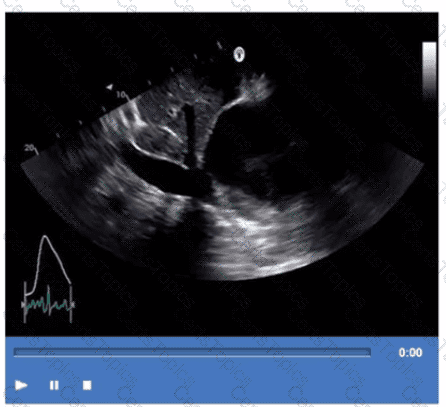

Based on this video, what is the estimated right atrial pressure in millimeters of mercury (mmHg)?

Which next step is appropriate after obtaining the Doppler signal in this image?